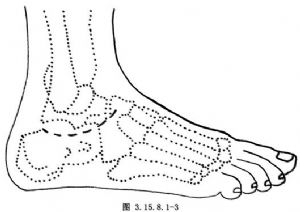

起自外踝下2cm,弧形向上,止于距舟关节的背外侧面(图3.15.8.1-3)。